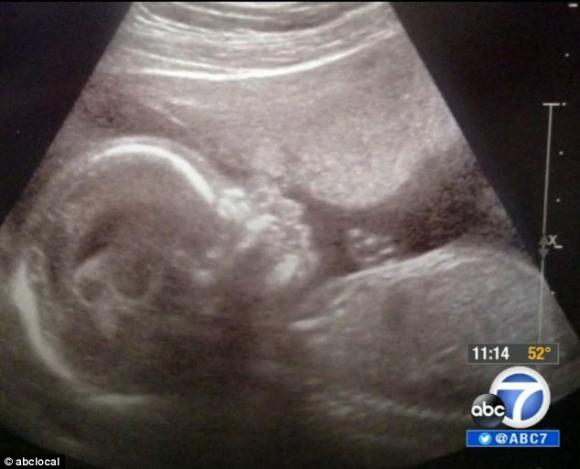

Các bác sĩ vô cùng ngạc nhiên với Hope Juarez, em bé “ma” chào đời có cơ thể trống tới 80% lượng máu.

Một cặp vợ chồng ở Irvine, California vừa trải qua cú sốc lớn bởi khi sinh con ra, đứa con của họ không hề có một giọt máu.

Khi mới sinh ra, toàn thân Hope tím tái và hầu như không hề có máu trong cơ thể.

Mắc một căn bệnh vô cùng hiếm gặp, cô bé Hope Juarez chào đời hầu như không có máu chảy trong cơ thể. 80% lượng máu trong cơ thể cậu bé đã bị chảy ra ngoài khi còn trong bào thai.

Các bác sỹ đã vô cùng hoảng hốt vì khi sinh ra Hope toàn thân tím tái và khi các bác sỹ đưa em vào phòng lấy máu để xét nghiệm, họ gần như không thể trích được một giọt máu.

Hiện đã được 6 tuần, Hope sống sót nhờ được bơm máu ngay lập tức sau sinh.

Nói về thai nhi trước khi chào đời, chị Jennifer Juarez, 27 tuổi, chia sẻ, “Con bé đạp rất nhiều, khoảng 10 lần trong 30 phút. Nhưng 3 tuần trước ngày sinh, dấu hiệu cử động của thai nhi hoàn toàn biến mất”.

Hope đã mắc phải hội chứng xuất huyết từ trong thai nhi. Duy nhất một trường hợp được biết đến mắc phải căn bệnh này mà sống sót là “em bé ma trắng” chào đời tại Anh vào năm 2012. Các dấu hiệu cũng tương tự như Hope, thai nhi hoàn toàn không cử động trong những ngày cuối cùng của thai kỳ.

Thai nhi đang cử động mạnh đột nhiên không đạp nữa là dấu hiệu chung của 2 ca em bé "ma" bị mất máu.

“Chúng tôi chưa xác định được rõ nguyên nhân dẫn đến hiện tượng này. Tình trạng thai nhi bị xuất huyết có thể xảy ra khi bà mẹ gặp tai nạn hay động thai. Tuy nhiên, chị Jennifer đều không bị các rủi ro trên. Do đó, rất khó phỏng đoán vì sao Hope lại bị xuất huyết trên 80%”, bác sĩ  Nguyễn cho hay.

Các bác sĩ cho biết, chị Jennifer đã cứu được mạng sống của con gái mình khi tới khám kịp thời vì phát hiện thai nhi không cử động nữa. Nếu chị chậm trễ một hoặc hai giờ đồng hồ nữa, Hope sẽ không còn trên cõi đời này như ngày hôm nay.